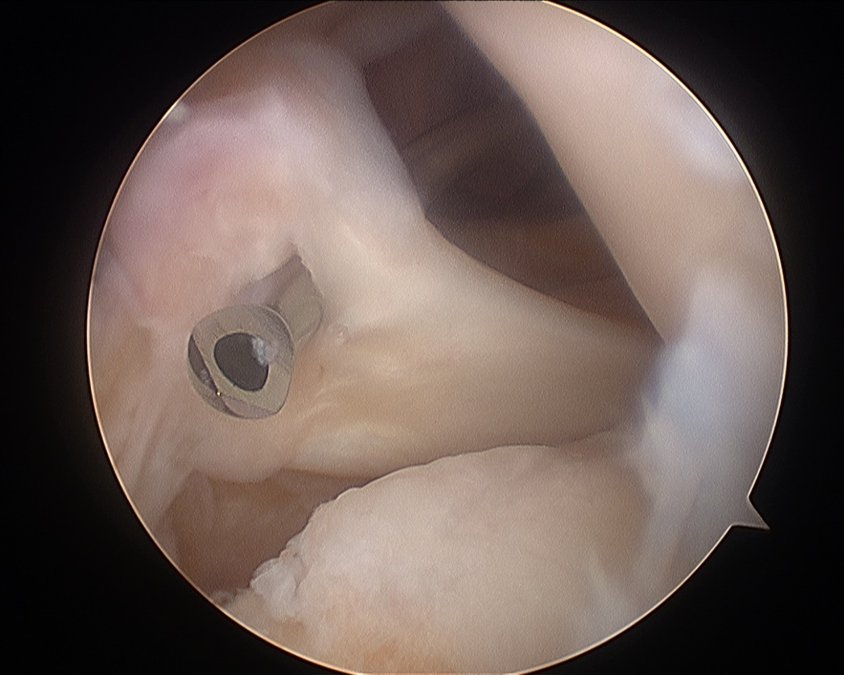

Technique

- use ACL guide

- pass under ACL / PCL to get to root insertion

- camera through posterolateral / posteromedial portal

- pass beath pin under vision

- pass endobutton drill under vision

- debride insertion